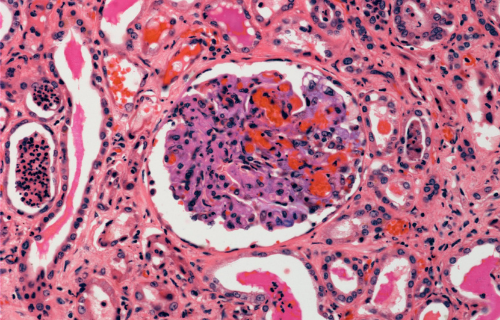

Necrosis is an unregulated and premature cell death. When this death results from blood flow blockage then this is referred to as infarction.

It is an uncontrolled premature cell death leading to swelling of the cell organelles, plasma membrane rupture and eventual lysis of the cell, and spillage of intracellular contents into the surrounding tissue leading to tissue damage.

Infarction is a type of necrosis or tissue death that is caused by a lack of blood supply to an affected area or cells.

Infarction is the process that results in an area of ischemic necrosis while necrosis is defined as any premature and unregulated cell or tissue death.